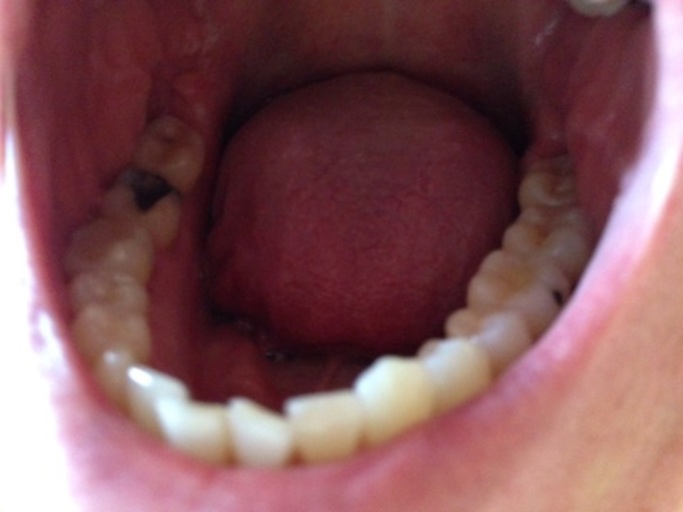

Do wisdom teeth need to come out only due to cavities.?

My 27 year old son has been told to now pull all 4 teeth. I am afraid because when he was a child he had a palate enlarger that ended up yanking out 4 baby teeth that did not stop bleeding! his teeth have shifted after invisalin. I'm afraid that he will have nerve and jaw problems and it seems his teeth will be free to shift more He got 3 cavities at the age of 25 for the first time so his teeth are not that bad. He seems to fall asleep at night without brushing. Can wisdom teeth be filled , and who can do it. We are on Long Island N.Y. Thanks, Bonnie